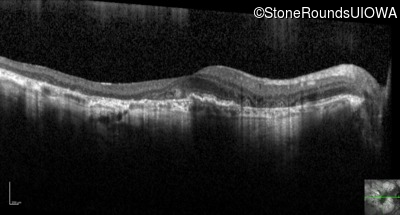

Optical Coherence Tomography - Right - 20/40 -2

Exemplar / OCT Stack

Optical Coherence Tomography - Left - 20/40 +1